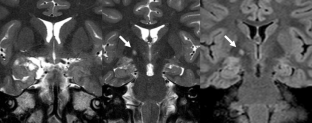

From a total of 61 DNTs, 48 simple and 13 complex variants were identified. Multiple or single pseudocysts in a cortical/subcortical location with small cysts sometimes separated from the tumor represented the glioneuronal element and were found in all DNTs. FLAIR hyperintense tissue was found between pseudocysts but—in neocortical DNTs—also circumscript in deeper tumor parts. Calcification and hemorrhages in this location occurred in four of 13 complex variants, and one of these patients was also the only one with tumor growth. Patients with complex variants had earlier seizure onset, and complex variants were more often located outside the temporal lobe. Although complex variants represented a higher diagnostic challenge, misdiagnoses also occurred in simple variants. One of five of DNTs showed contrast enhancement, which varied on follow-up studies with enhancing parts becoming nonenhancing and vice versa.